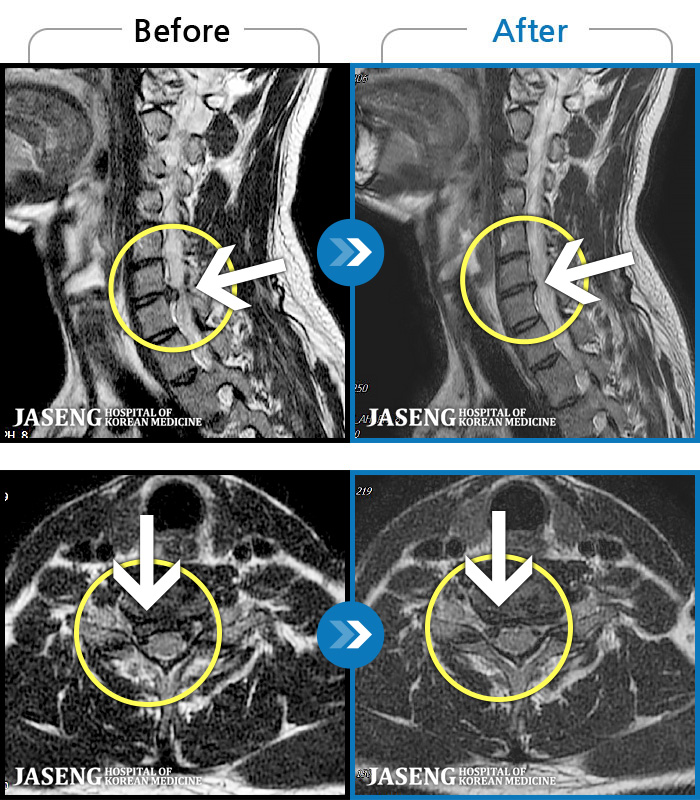

ȯںп Ǹ ǿ ԿǾ, ο ġ ۿ Ƿ ġḦ Ͻñ ٶϴ.